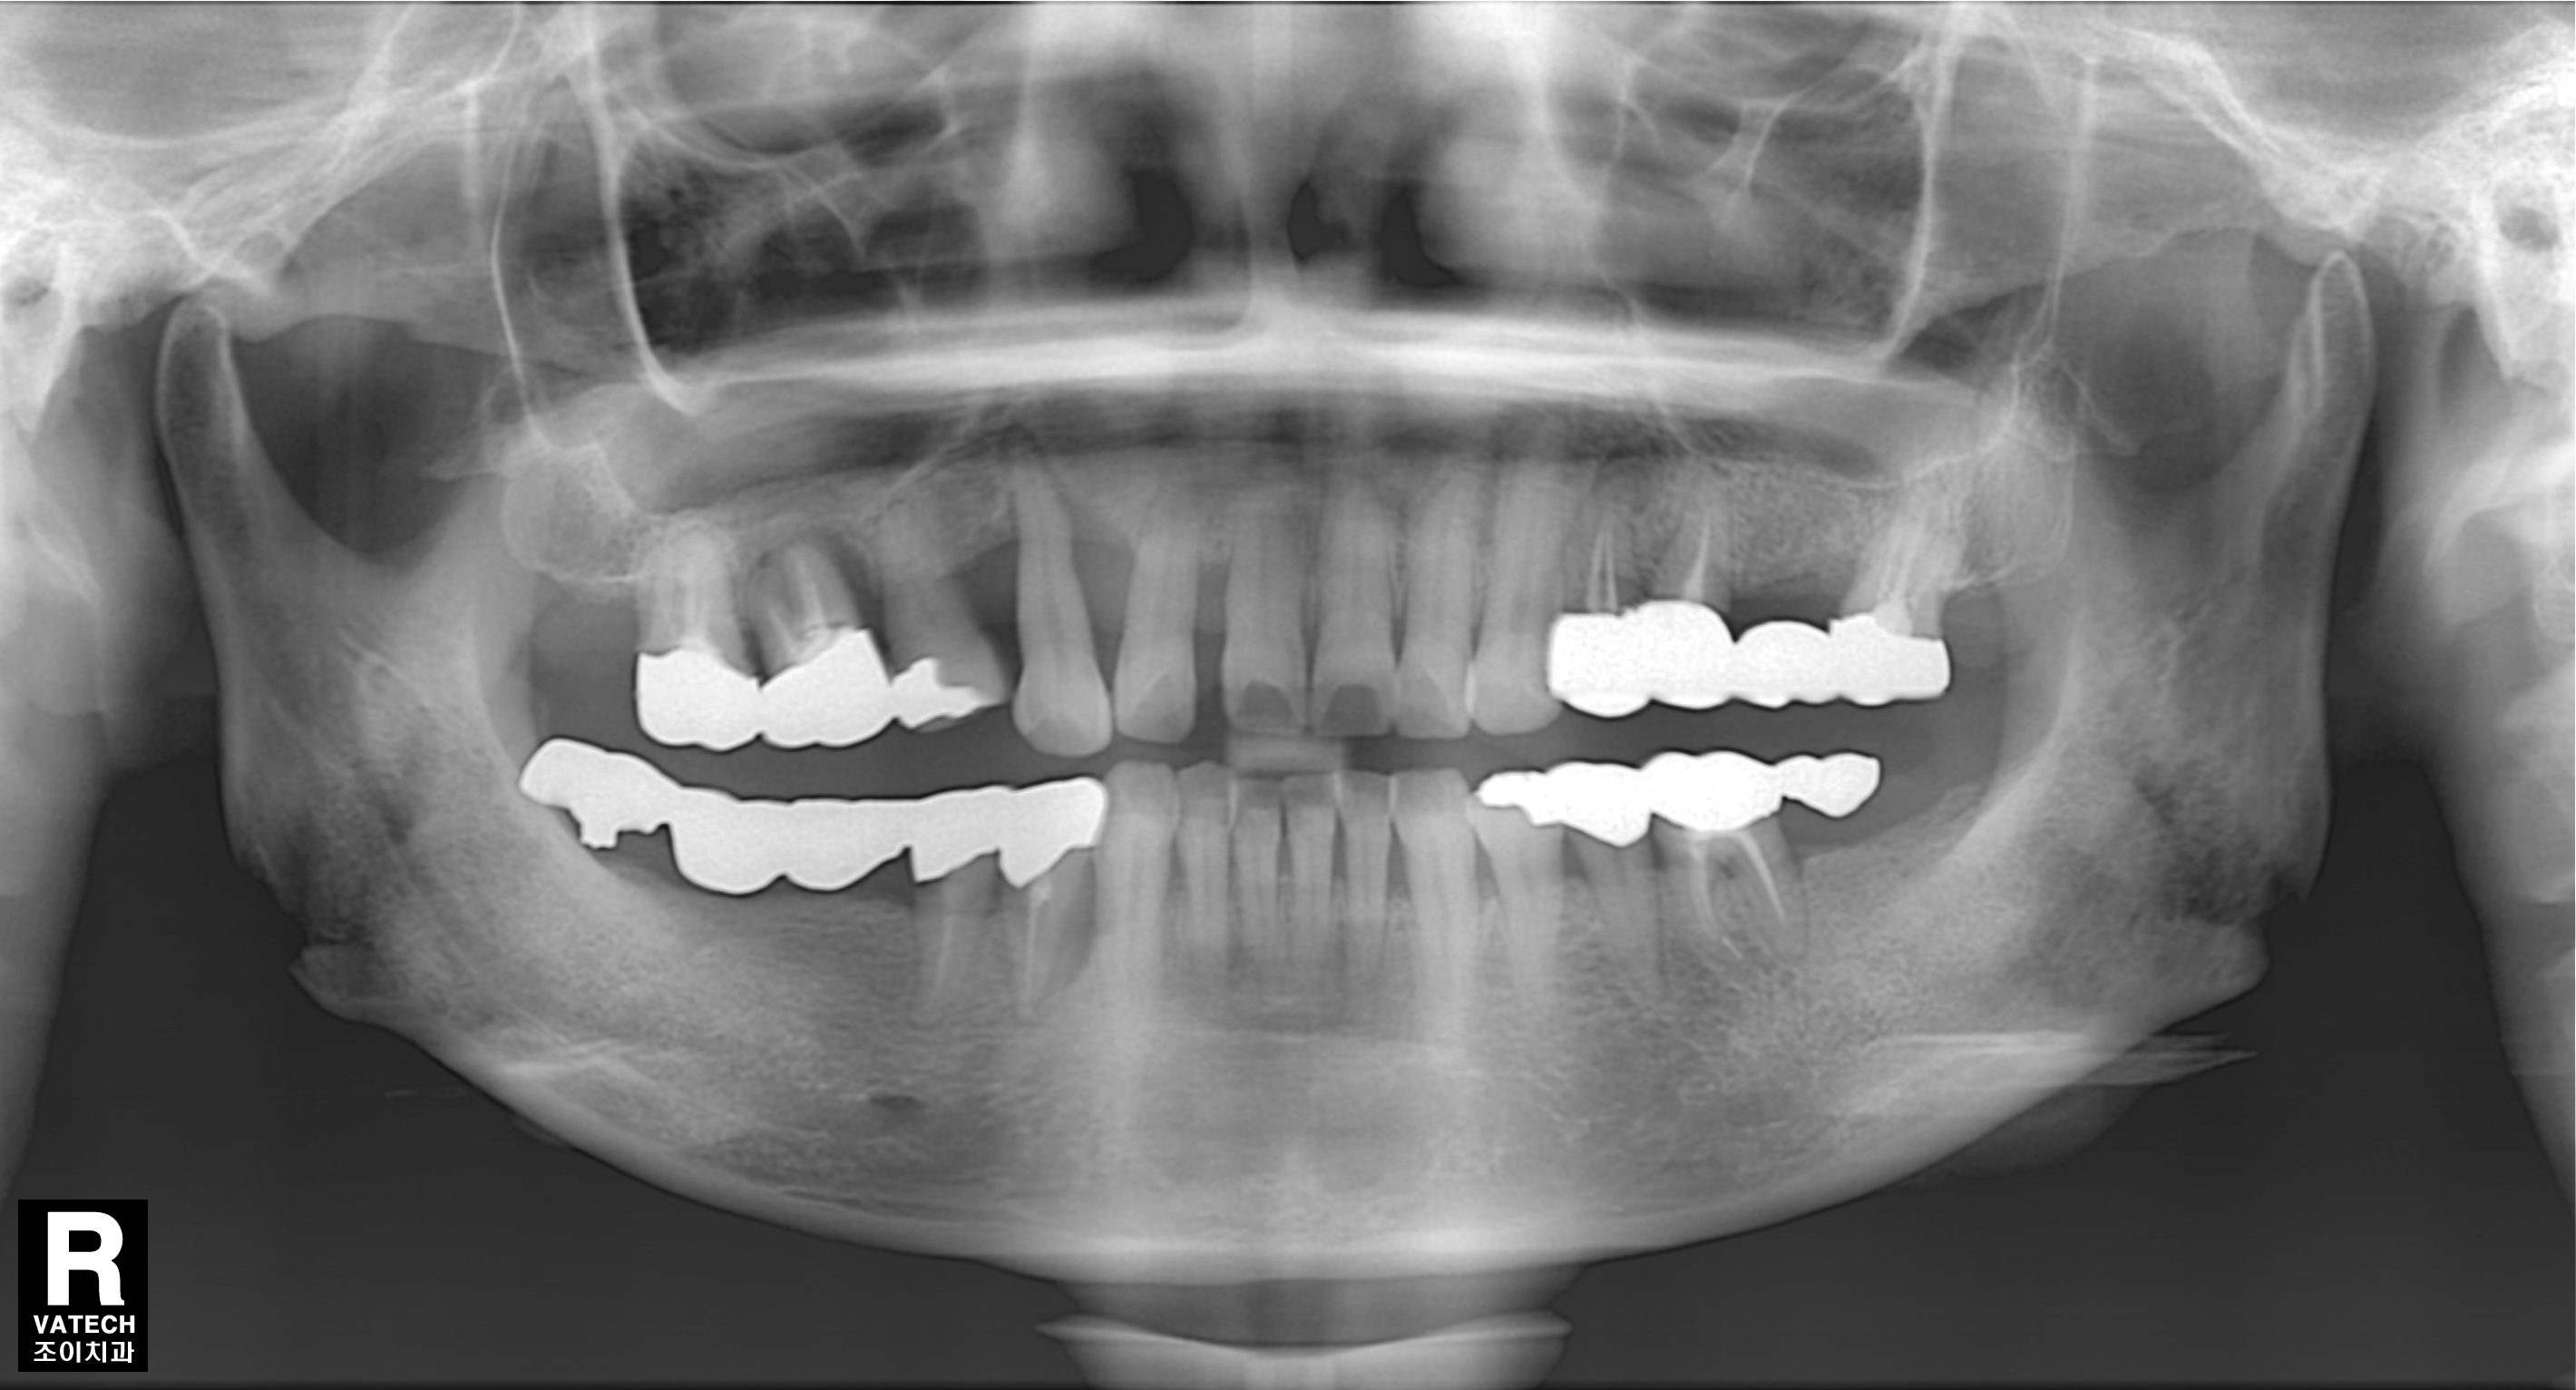

[임플란트] 제목 : 임플란트에 의한 교합기능 재건

임플란트에 의한 교합기능 재건